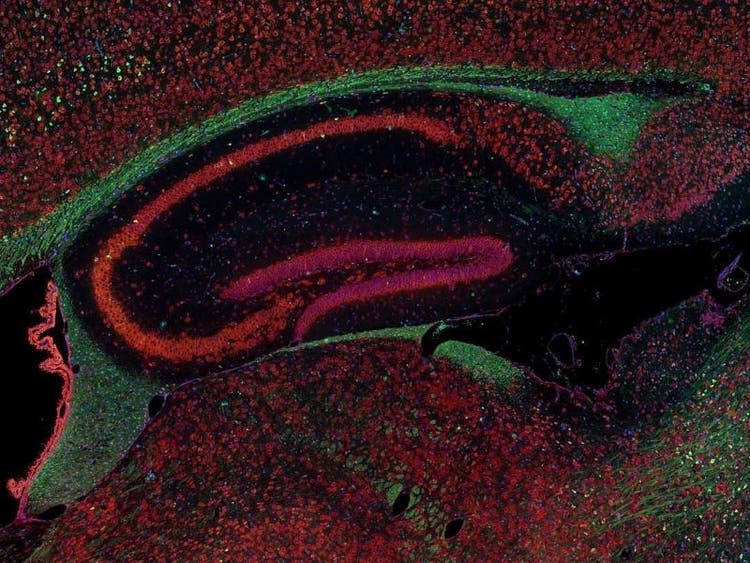

Fluorescence imaging of a mouse brain

While each of these images looks distinct up close, they all come together to form one view of a mouse brain captured with fluorescence imaging.